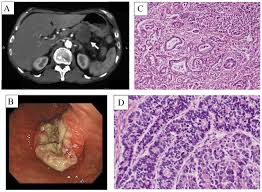

Pankreas Adenokarsinomu (PAC), modern onkolojinin en ölümcül ve dirençli kanser türlerinden biridir. Bu kanserin düşük yaşam süresinin (%9) ana nedeni, tümör hücresinin kendisinden ziyade, onu çevreleyen ve koruyan karmaşık savunma sistemidir. Bu sistemin merkezinde ise Kanser İlişkili Fibroblastlar (CAFs) bulunur.

Pankreas kanseri, çevresinde aşırı yoğun ve sert bir bağ dokusu (stroma) biriktirir; bu duruma desmoplastik reaksiyon denir.

Zırhın Bileşenleri: Bu sert siperin ana hücreleri CAFs'lerdir. CAFs'ler, Kollajen ve Hiyalüronik Asit (HA) gibi Hücre Dışı Matriks (ECM) proteinlerini aşırı üreterek tümör etrafında fiziksel bir bariyer oluşturur.

Direnç Etkisi: Bu "Fibrotik Kalkan", damarları sıkıştırır, ilaçların (kemoterapi) tümör merkezine ulaşmasını engeller (penetrasyonu azaltır) ve radyoterapiye karşı direnci artırır. Bu sert matris aynı zamanda tümörün agresifliğini destekler.

Pankreas kanserinde (PDAC) kanserle ilişkili fibroblastlar (CAF'ler) çeşitli hücrelerden kaynaklanır. PSC'ler ve diğer yerleşik doku fibroblastları, kanserle ilişkili fibroblastlara dönüştürülebilir. Tümör mikroortamındaki sitokinler ve kemokinler, MSC'lerin, perisitlerin ve adipositlerin CAF'lere farklılaşmasına ve tümöre çekilmesine neden olabilir. Kemik iliğinden türetilen makrofajların bir alt kümesi, CAF benzeri hücrelere dönüşerek pankreas kanseri ilerlemesini destekler. Transdiferansiyasyon, epitel, endotel ve mezotel hücrelerinin CAF popülasyonuna katılmasını sağlar. myCAF, iCAF ve apCAF, PDAC'de keşfedilen farklı CAF fenotipleridir. myCAF, tümöre yakın bir konumda bulunurken, iCAF tümörden daha uzaktadır; apCAF ise tümör mikroortamında immün baskılamayı destekleyen daha küçük bir alt kümedir.

CAF'ler, ECM bileşenlerini salgılar ve fibrotik tümör mikroortamına katkıda bulunur. SHH, TGF-β, IL-1, PDGF ve HIF-1 gibi kanser hücresi kaynaklı sitokinler, CAF aktivasyonunda önemlidir ve aktive olmuş CAF'ler, tümör oluşumunu destekleyici faktörler salgılayarak kanser hücresi proliferasyonunu teşvik eder. Ayrıca, PDAC hücreleri tarafından salınan eksozomlar, CAF'lerin toplanmasına ve aktivasyonuna yardımcı olabilir. Pankreatik CAF'ler, IL-6, CXCL2, CXCL12 ve CXCL8 gibi faktörler salgılayarak inhibitör immün mikroortamın oluşumuna katkıda bulunur. CAF'ler sadece immün baskılayıcı hücrelerin toplanmasından ve düzenlenmesinden sorumlu olmakla kalmaz, aynı zamanda immün kontrol noktası belirteçlerini artırarak CD8+ T hücrelerinin anti-tümör fonksiyonlarını yerine getirmesini de engeller.

CAF'ler, kötü huylu hücrelerin besin eksikliğinin üstesinden gelmesine yardımcı olur. Tümör hücrelerinin etkisi altında, CAF'ler aerobik glikoliz gerçekleştirir ve pankreas adenokarsinomu (PDAC) hücrelerine besin sağlar. Dahası, CAF'lerden türetilen kolajenler ve hücre dışı matristeki hyaluronik asit (HA) de tümör hücreleri tarafından kullanılabilir. Ayrıca, CAF'ler kötü huylu hücrelerin metabolizmasının yeniden programlanmasına katkıda bulunur. CAF'ler tarafından salınan eksozomlar da PDAC hücrelerindeki metabolizmayı besleyebilir. Dahası, CAF'ler ottofajiye katılarak mitokondriyal metabolizma ve tümör büyümesi için alternatif karbon kaynakları olarak hizmet eden enerji açısından zengin metabolitler üretir.